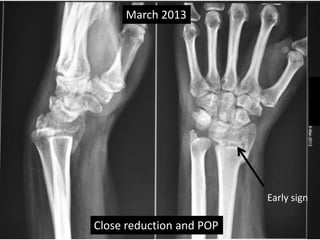

Case one

• 42 years old female.

• Low energy trauma.

• Fracture lower end radius

• Treated conservatively by closed reduction

and pop casting in Dec 2012.

Dec 2012

March 2013

Close reduction and POP

Early sign

Case one •42 years old female. • Low energy trauma. • Fracture lower end radius • Treated conservatively by closed reduction and pop casting in Dec 2012.

March 2013 Closereduction and POP Early sign